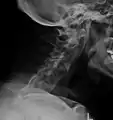

Lateral X-ray of the neck in ankylosing spondylitis

The earliest changes demonstrable by plain X-ray shows erosions and sclerosis in sacroiliac joints. Progression of the erosions leads to widening of the joint space and bony sclerosis. X-ray spine can reveal squaring of vertebrae with bony spur formation called syndesmophyte. This causes the bamboo spine appearance. A drawback of X-ray diagnosis is the signs and symptoms of AS have usually been established as long as 7–10 years prior to X-ray-evident changes occurring on a plain film X-ray, which means a delay of as long as 10 years before adequate therapies can be introduced.[24]

Options for earlier diagnosis are tomography and MRI of the sacroiliac joints, but the reliability of these tests is still unclear.